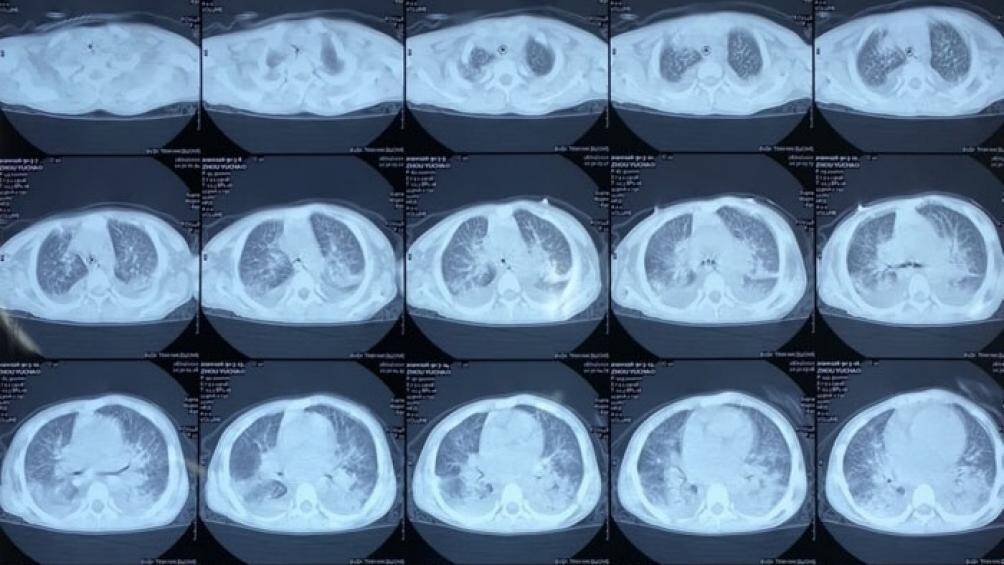

Hình ảnh chụp phổi của bệnh nhân

Trước đó, tối 26/1, Bệnh viện đa khoa tỉnh Hải Dương tiếp nhận bé Zhou Yuchao (10 tuổi, quê ở tỉnh Hồ Nam, Trung Quốc) được chuyển đến từ Trung tâm Y tế huyện Gia Lộc trong tình trạng khó thở, niêm mạc nhợt nhạt, da tím tái, không sốt. Qua chẩn đoán hình ảnh, hội chẩn, bệnh nhân được kết luận suy hô hấp, viêm phổi, có tiền sử suy thượng thận bẩm sinh, chưa loại trừ khả năng bị phù phổi.